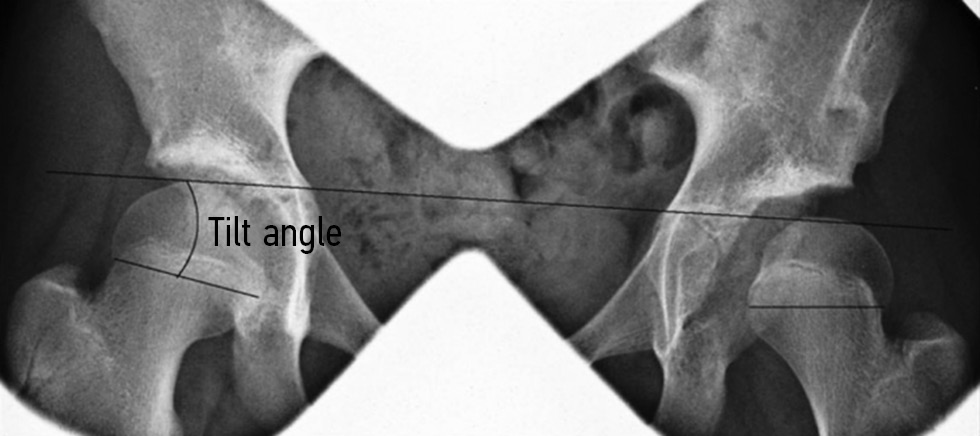

In 2011. McGillion and Clarke developed additional radiological criteria to the existing ones to objectify the indications for epiphysiodesis [21–23]. They defined the following radiographic criteria to evaluate epiphyseal displacement in necrosis on anteroposterior pelvic radiographs: the angle between the Hilgenreiner line and line along the edges of the epiphysis of the femoral head. A change in the angle between these lines indicates displacement of the femoral head in relation to the pelvis, which makes it possible to suspect aseptic necrosis and deformation of the lateral growth zone over time. The authors do not give the normal values of this angle; however, note that in the norm, this angle is positive (>0), and in pathology, it decreases and the lines become parallel (Fig. 2).

Fig. 2. Determination of the tilt angle [24]

This criterion is called the “tilt angle.” When evaluating postoperative radiographs and following up with patients, the change in this angle allows us to assess the dynamics of the effect on the growth zone and the degree of correction of the deformity, which is what the authors presented in their study. However, they noted that the “tilt angle” is a two-dimensional analysis, whereas CT scans can assess the magnitude of anteversion in addition to the valgus deformity. CT further showed that the bony bridge of the disturbed growth zone can be located in both the posterolateral and anterolateral parts of the epiphysis of the head. Thus, the concomitant torsional deformity of the femur complicates the prediction of the efficacy of medial epiphysiodesis, and a more thorough examination of the patient is required [24].